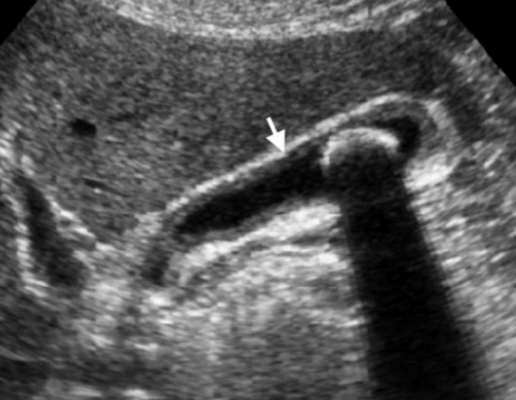

(Левый) На продольном косом УЗ срезе у пациента с острым веска менным холециститом с гангреной, перенесшего трансплантацию легкого, визуализируется растянутый желчный пузырь, содержащий вязкий сладж. Стенка желчного пузыря утолщена, ее контур имеет дефекты.

(Правый) На продольном косом срезе у того же пациента определяется гиперемия перипузырной зоны, признаки кровотока в некротизированной стенке отсутствуют.